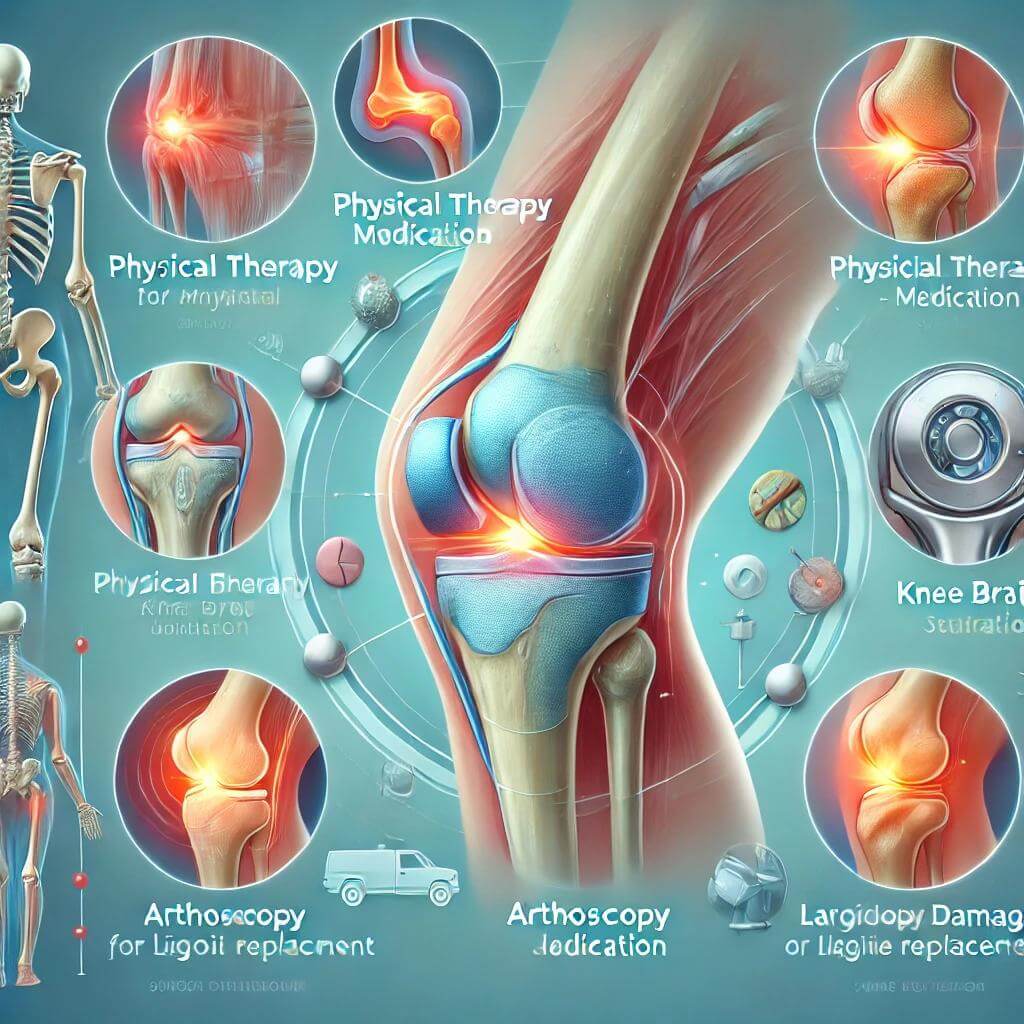

1) 휴식과 물리치료: 가벼운 무릎 통증은 휴식과 물리치료를 통해 충분히 관리할 수 있습니다. 물리치료는 근육을 강화하고, 무릎 관절에 가해지는 부담을 줄여주는 역할을 합니다. 또한, 무릎에 무리가 가지 않도록 적절한 스트레칭과 운동법을 배우는 것이 중요합니다.

2) 약물 치료: 통증이 심할 경우, 소염제나 진통제를 복용하여 염증을 줄이고 통증을 완화할 수 있습니다. 그러나 약물은 일시적인 해결책이므로 장기적인 치료를 위해서는 물리치료나 생활 습관 개선이 병행되어야 합니다.

3) 주사 치료: 스테로이드 주사는 무릎의 염증을 줄이고 통증을 일시적으로 완화하는 데 효과적입니다. 또한, 히알루론산 주사는 관절액을 보충하여 무릎의 움직임을 개선할 수 있습니다. 이러한 주사 치료는 퇴행성 관절염이나 연골 손상 환자에게 자주 사용됩니다.

4) 수술: 무릎 관절이 심하게 손상되었을 경우, 인공관절 수술이나 관절경 수술을 고려해야 합니다. 인공관절 수술은 손상된 관절을 인공 관절로 대체하는 수술로, 통증을 크게 줄이고 무릎 기능을 개선할 수 있습니다. 그러나 수술은 마지막 수단으로, 다른 치료 방법이 효과가 없을 때 시행됩니다.